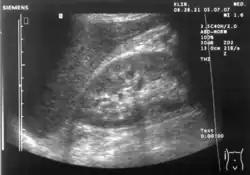

Ultrasonographic view of the abdomen demonstrating fluid within Morison's pouch -